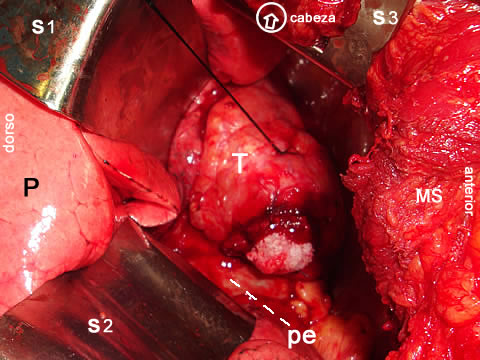

Abordaje por Toracotomía derecha

Para tener una amplia exposición del tumor en su relación Mediastinal, se abordó mediante una incisión de toracotomía derecha posterolateral, a la exposición del mediastino observamos un tumor de unos 10 cms, de diámetro por unos 6 cms de espesor, aspecto lobulado, superficie fibrosa muy vascularizada, y engrosada, su extremo anterior adherido ó involucrado al segmento lingular inferior del lóbulo medio el cual se reseco, le proveía de amplia vascularidad; en su pared interna adosado al pericardio sin invadirlo y en su extremo posterior, adosado al hileo pulmonar mediante  disección mixta, se logro liberar de la arteria pulmonar derecha quien le aportaba alguna vascularidad, de la cava superior en la que discurría el nervio frénico derecho y en el lado derecho de la aorta ascendente y por su limite inferior del pericardio auricular. constatada la hemostasia, Se colocó un drenaje torácico por contrabertura para drenaje y expansión pulmonar y procedimos a la síntesis por planos de la manera usual.

Fotografía A:  la exposición del mediastino desde Toracotomía postero lateral derecha, en la foto: la cabeza del paciente va situada arriba, el frente del paciente a la derecha y el dorso a la izquierda.

T.- el Tumor mediastino con punto de seda para manipulación, luego de la disección y resección del segmento lingular inferior del lóbulo medio,

P.- el pulmón derecho separado por las valvas S1 y S2.

pe - el pericardio auricular.

MS - Músculo serrato anterior de la pared costal,

S3 - valva separando la aorta ascendente para exposición fotográfica de la lesión